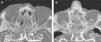

MethodsA descriptive study was performed including CT images of 20 cadaver heads. The specimens were perfused with a radiopaque material and various anatomical parameters were analysed.

ResultsThe anterior ethmoidal artery was found in 95% (38/40) of cases. It originated from the ophthalmic artery in 87.5% (34/40) of nasal cavities. In six cases, normal variants were found. The mean length of the anterior ethmoidal canal was 8.43±0.74mm. The angle performed into the skull base was 37.3±5.48°. In 90% of cases (36/40), it was located between the second and third lamella. The posterior ethmoidal artery was localised only in 14/40 cases, with 28.5% (4/14) of them showing normal variants. The mean length of the posterior ethmoidal canal was 7.1±1.02mm. The angle performed into the skull base was 7.11±4.07°. The distance from sill to the anterior ethmoid artery was 55.51±5.52mm. The angle between the nasal spine and the anterior ethmoidal canal was 57.67±1.68°. The distance between the nasion and the anterior ethmoidal canal was 29.31±2.53mm, the distance was 11.24±2.14mm from the anterior ethmoid artery to the posterior ethmoid artery and from the posterior ethmoid artery to the optic nerve, 7.26±1.33mm. Supraorbital cells were observed in 15% (6/40) of the cases.